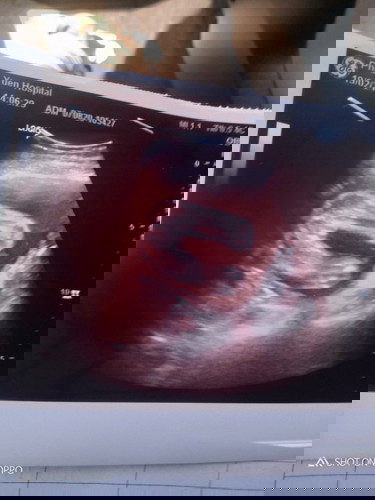

กลีบชัดมากเลยค่ะ เหมือนตอนแม่ซาวด์เลย